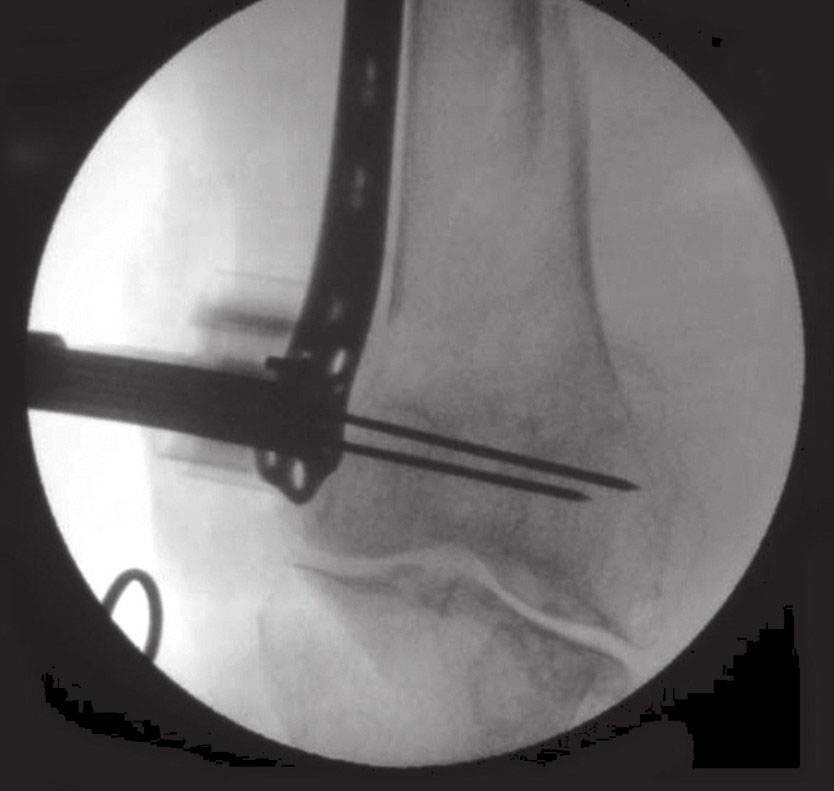

在图像增强器下用手法牵引进行骨折复位

借助股骨撑开器进行肢体长度恢复和复位的维持

在透视机下手法牵引复位骨折。良好的复位关键在于骨长度、轴线和旋转的复位。若手法复位不能良好复位,可借助股骨牵引器置于腿部前侧或外侧进行精确的长度复位,并保持复位的位置。